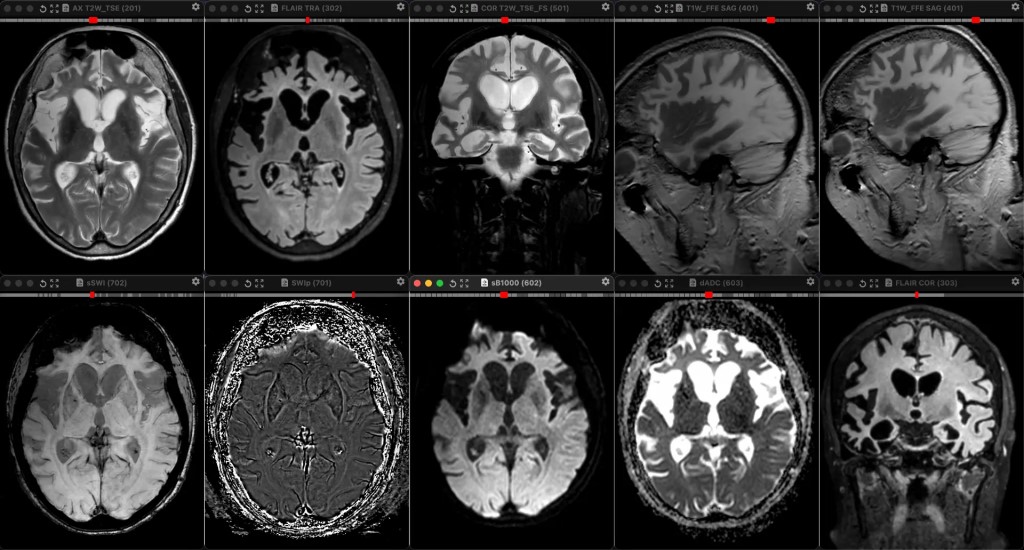

Фото девушка 65 лет. Болезнь Пика классическая (даже без знания клиники) - фронтотемпоральная дегенерация: выраженная, асимметричная, как обычно и бывает, атрофия лобных и височных долей. Перестала вообще говорить, на контако не выходит. Грубая деменция.